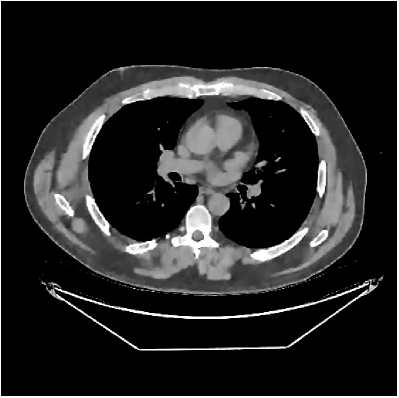

This section compares the reconstruction quality and runtime among the proposed MBIR method, PWLS-ST-, and other three MBIR methods, PWLS-EP, PWLS-DL, and PWLS-ST-. Table I shows that, for both 2D and 3D sparse-view CT reconstructions of the XCAT phantom, the proposed PWLS-ST- model outperforms PWLS-EP and PWLS-ST- in terms of RMSE. In addition, PWLS-ST- using a square transform (of size ) achieves lower RMSE than PWLS-DL using an overcomplete dictionary (of size ) for 2D sparse-view reconstructions. Fig. 3(a) and Fig. 4 show the reconstructed images for 2D and 3D phantom experiments, with different reconstruction models and different number of views. (See the corresponding error maps in the supplement.) The proposed PWLS-ST- consistently gives more accurate image reconstructions compared to other MBIR methods. Specifically, PWLS-ST- has smaller errors in the heart region (see zoom-ins in Fig. 3(a)) of 2D reconstructions than PWLS-DL and PWLS-ST-. In addition, compared to PWLS-ST-, PWLS-DL and PWLS-ST- have some ringing artifacts around the edges with high transition, e.g., edges between air and soft tissues. (See a comparison of profiles of PWLS-ST- and PWLS-ST- in the supplement.) In particular, PWLS-ST- and PWLS-DL give more visible ringing artifacts for 2D reconstruction from fewer views, and PWLS-ST- has these ringing artifacts for 3D reconstructions regardless of the number of views (see zoom-ins in Fig. 4). Table II reports runtimes of different MBIR methods in reconstructing the -views XCAT phantom scan. (FBPConvNet is a non-MBIR method and its runtime for processing a image is approximately one second with a TITAN Xp GPU.) While providing better reconstruction quality, the proposed Algorithm 1 of PWLS-ST- has shorter runtime compared to the algorithms of PWLS-DL and PWLS-ST- in Section III-A. Similar to the PWLS-EP algorithm, the reconstruction time of the PWLS-DL, PWLS-ST-, and PWLS-ST- algorithms can be further reduced by using ordered subsets [51].

| (b) 3D axial cone-beam CT experiments |